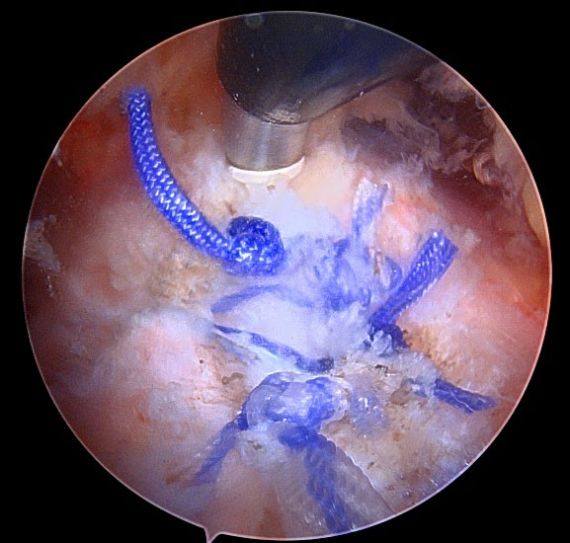

Operative Treatment for Proximal Hamstring Tears

Minimally invasive surgery can be performed either through one small incision in the posterior thigh (as seen below) or through 3-4 poke hole incisions with the use of a camera and special instruments. The tendons are reattached to the posterior pelvis (ischium) with suture anchors.